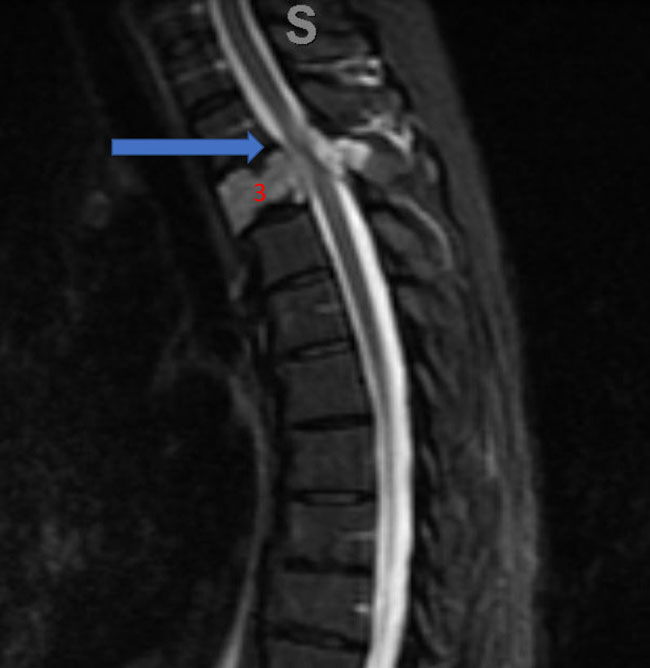

Figure 1. A) Sagittal T2 MRI demonstrates aggressive hyperintense T3 hemangioma involving the body and posterior elements compressing the thoracic spinal cord (arrows)

He presented to the emergency room with one-week history of thoracic pain in addition to bilateral lower extremity weakness and paraparesis. MRI imaging with contrast showed a diffuse abnormal signal within the vertebral body of T3 and the posterior elements with lobulated soft tissue lesion extension into both paraspinal areas (Figure 1. A, B, C).